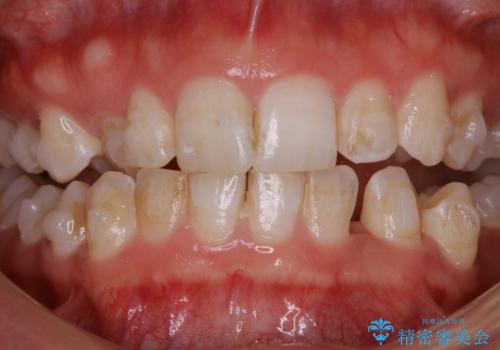

- 毎日の歯磨きの際に出血する。歯科でにクリーニンングをしばらくしていないとのことでした。PMTC60分コースを行いました。

歯磨きの際の出血は、歯肉炎や歯周病の症状とも言えます。歯周ポケットに歯周病菌が棲みつき、歯周病菌の出す毒素が歯茎に炎症を起こします。炎症が拡大し、歯周組織が破壊されたまま放置すると、最悪の場合、歯を支えている骨が溶かされ、歯がぐらぐらしてきます。

そのため重要なのが、毎日の歯磨きで可能な限り汚れを取り除くこと・定期的に歯科医院で歯周病の検査をしたり、歯石除去や歯茎の炎症を取り除くことです。